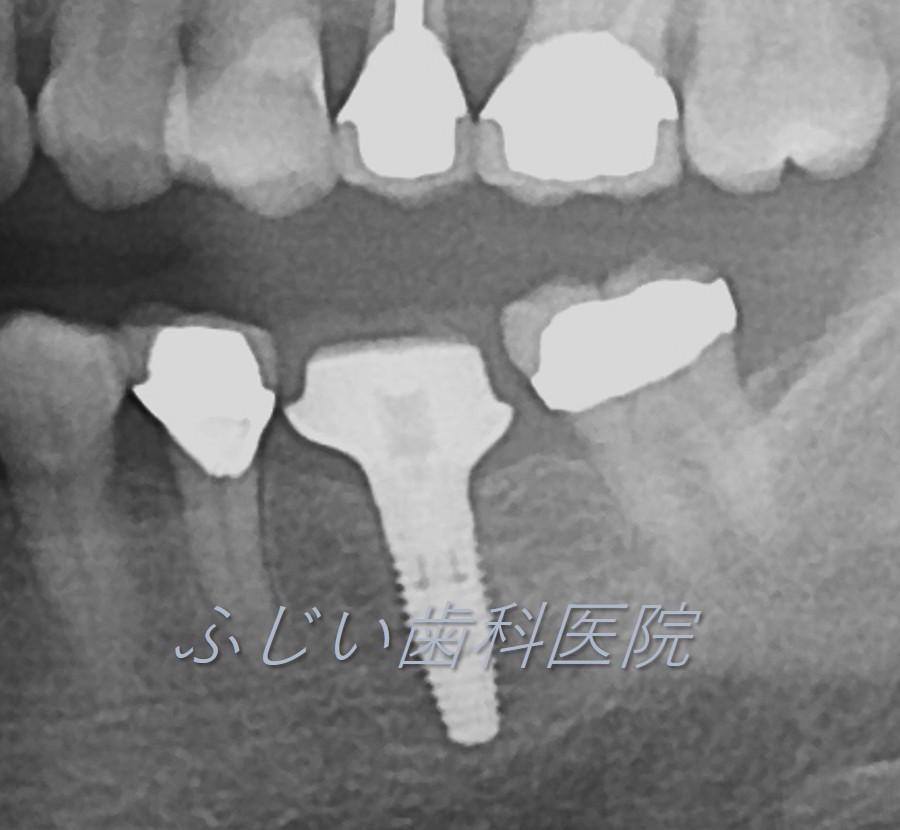

STEP 2 1次オペ(インプラント埋入手術)

インプラントを埋入する部位の歯肉を開き、顎の骨にインプラントを埋入します。

インプラントが骨にしっかり結合するまで約2~6ヶ月待ちます。

STEP 3 2次オペ(ヒーリングアバットメント装着)

歯肉を開き、人工歯(被せ物)を支えるためのヒーリングアバットメント(仮の土台)をインプラントに装着します。(歯肉の傷が治癒するまで約3週間待ちます。)

STEP 4 アバットメント(土台)・仮歯装着

アバットメント・仮歯を作製する為に、1~2回歯型を取り、装着します。

STEP 5 人工歯の完成

仮歯で問題がなければ、再度歯型を取り、最終的な人工歯を作製し、アバットメントに装着して完成です。

(インプラント埋入~完成まで、早くて3カ月ほどの期間がかかります。)